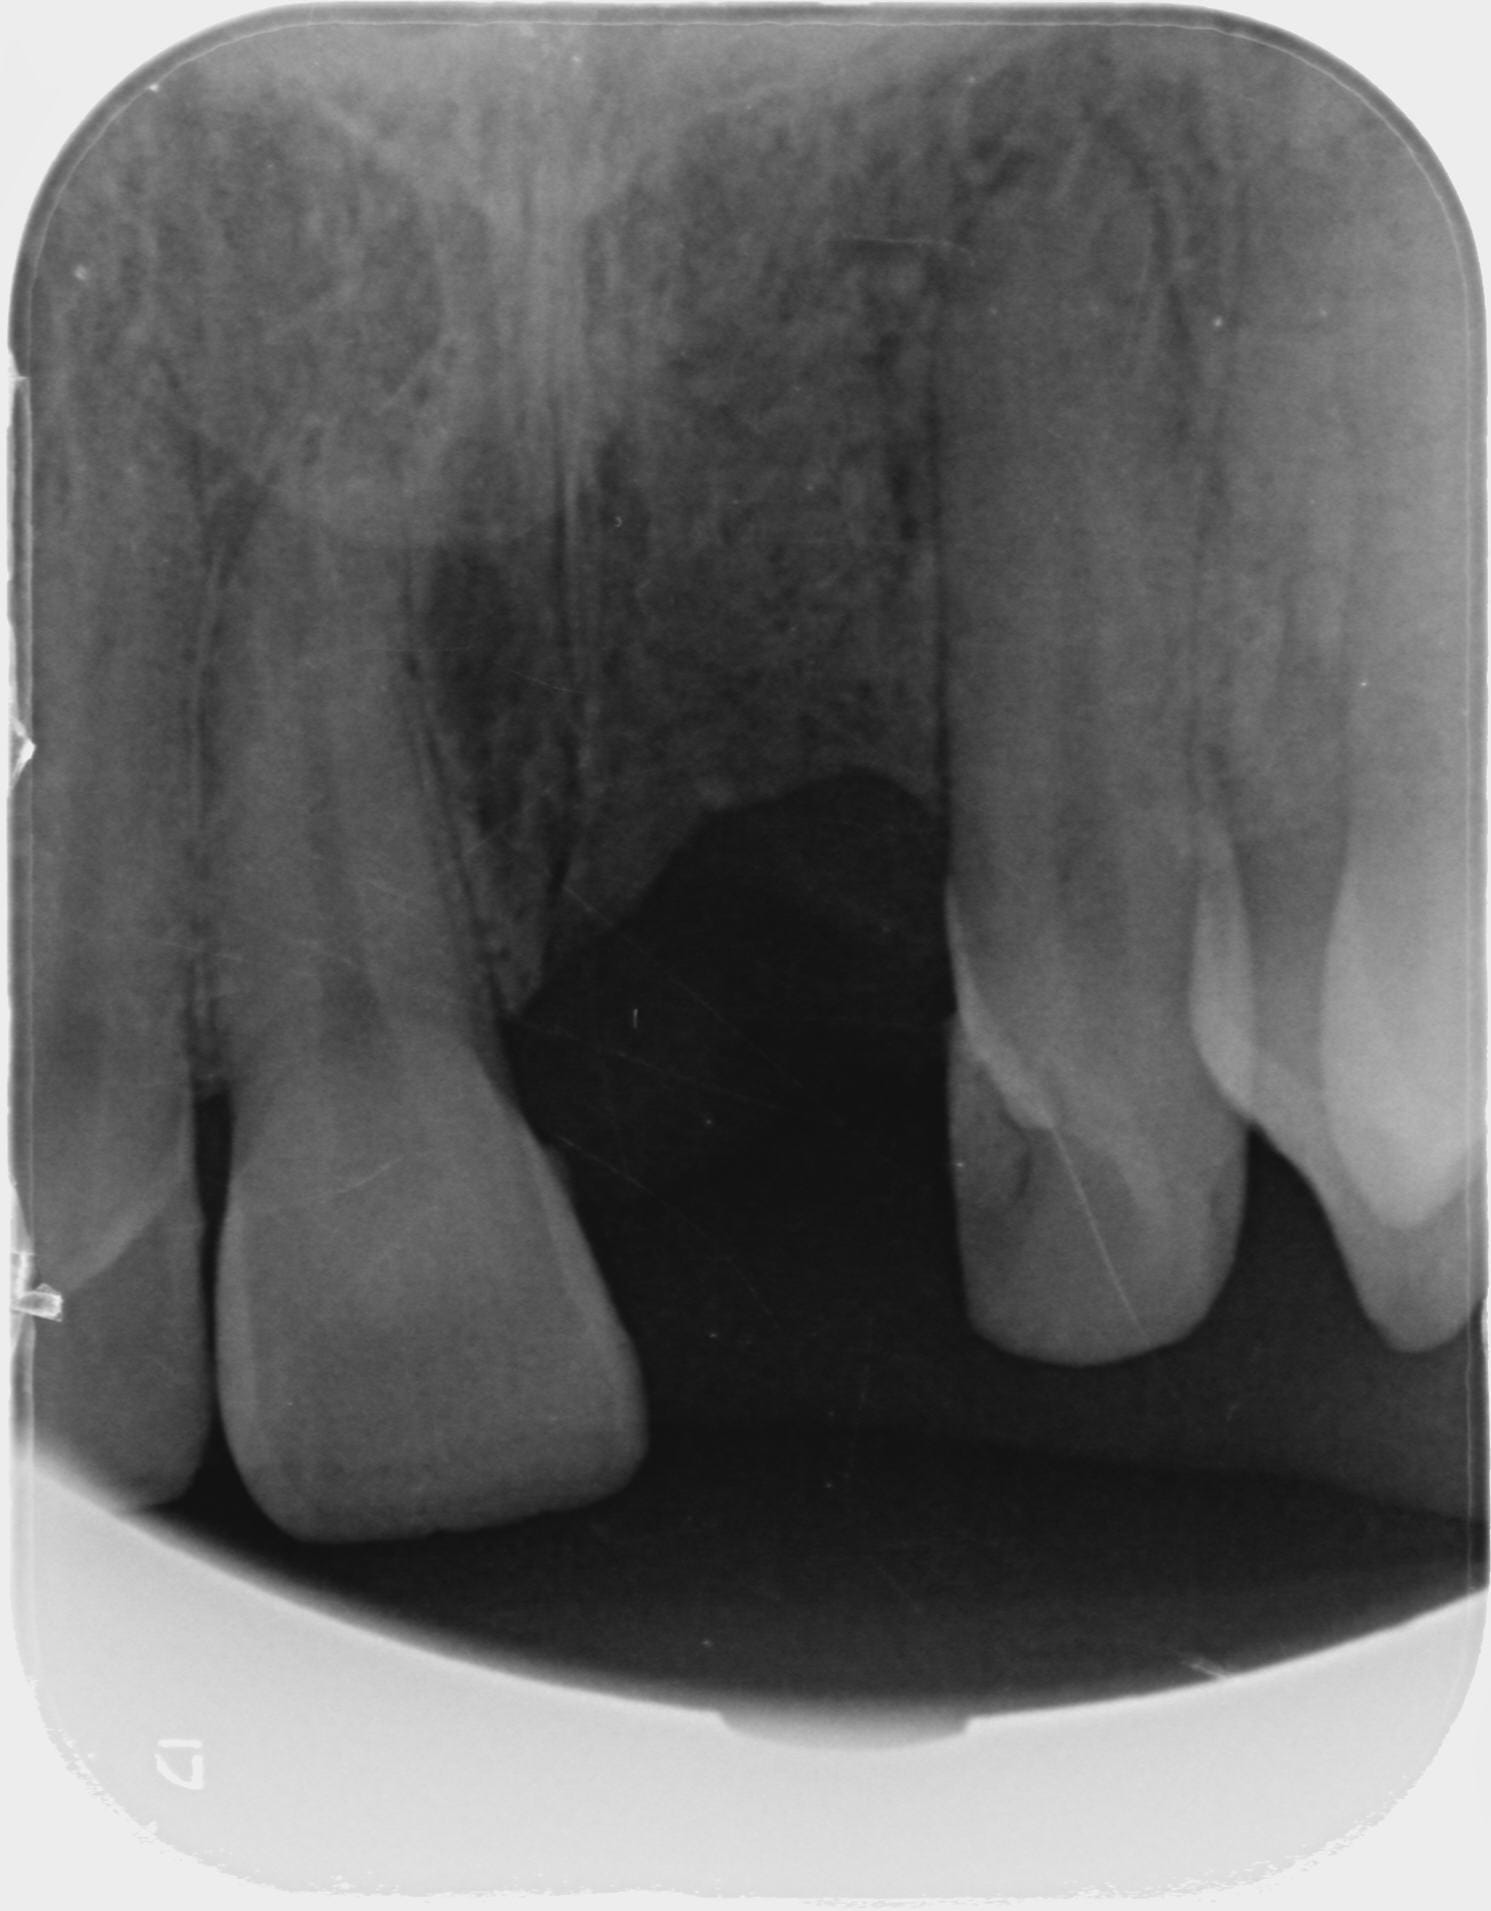

Les rétros

2015 05 29 retro avant exo x9afby - Eugenol

2017 01 04 exo uklgb2 - Eugenol

2017 05 03 retro preop dadb2g - Eugenol

2017 11 09 retro jour pose hwdyvj - Eugenol

2017 11 15 retro j 7 x3s3zc - Eugenol